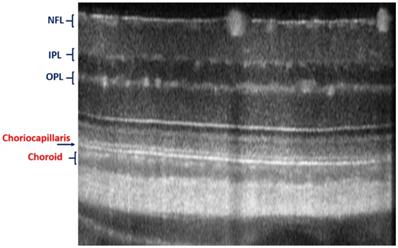

Figure 6

In vivo imaging of microvasculature layers and depth localization through pv-OCT/SLO system. Micrographs showing pv-OCT/SLO imaging showing images visualized at different layers such as nerve fiber layer (NFL), inner plexiform layer (IPL), inner nuclear layer (INL), outer plexiform layer (OPL), outer nuclear layer (ONL), inner segment (IS), outer segment (OS), retinal pigment epithelium (RPE), and choroid, respectively. (Adapted from Goswami et al. 2016 [163]).

The advantages of these two systems have been complied with the natural optical systems like in mouse eye, amalgamating their capabilities, and promotes in vivo mouse studies for probing the structural and functional information of the retinal unit [117,118]. The utilization of such fusion adaptive optics (AO) for imaging is an ongoing revolution in bio-imaging research in which structural and functional visualization of cells can be done in vivo through the genetically encoded optical probes[119]. AO-SLO is one of the most appropriate imaging biomarkers used in recent times designed exquisitely for the fluorescence and reflectance imaging of the retina of the mouse [101]. The utility of this imaging system could be demonstrated for the imaging of retinal capillaries, microglia, retinal blood flow, and cone photoreceptor cells, which collectively exhibit green fluorescence protein (GFP). This further illustrates the localization and visualization of the morphological structures and cells in 3D by combining the AO-SLO data with wide field OCT/phase variance OCT and SLO data. The studies performed on such a combined imaging system reported the extensive differentiation and visualization of microvascular retinal layers, choriocapillaris represented in Figure 5 and Figure 6, respectively.